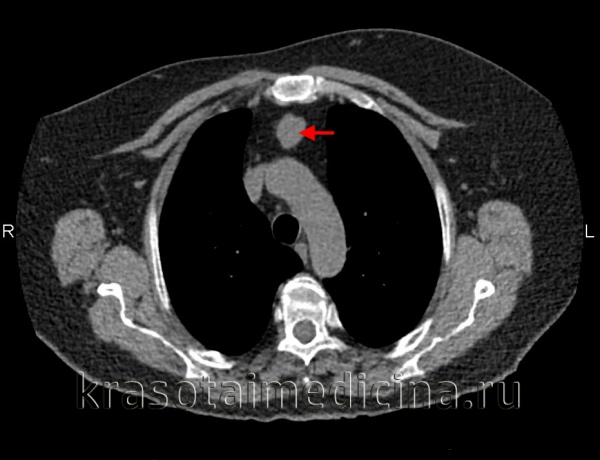

Последовательно выполненные рентгенограммы:

а — напряженный пневмомедиастинит (указан стрелками). Необычно массивное скопление в средостении;

б — успешно установленный дренаж (указан стрелкой).